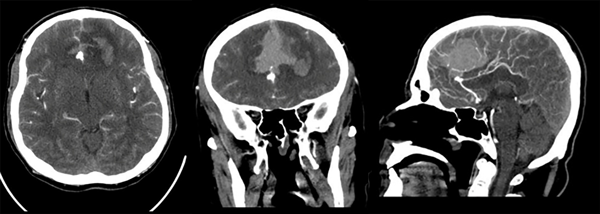

Paciente masculino de 47 años sin antecedentes patológicos de importancia, refiere inicio de enfermedad actual con cefalea súbita, severa, holocraneana, irradiada a región occipitocervical con vómitos en proyectil, desorientación, midriasis e incontinencia urinaria; es remitido a nuestra institución a los 16 días desde el inicio de los síntomas. Al ingreso se observa meningismo, trastornos en el nivel de conciencia e hipertensión arterial. En la tomografía de cerebro (TC) se observa una hemorragia subaracnoidea con un hematoma frontal bilateral. Se realiza angiotomografía cerebral donde se evidencia aneurisma sacular mediano trilobulado de ACAa (Figuras 1 y 2). Al examen físico de ingreso: bradipsíquico, bradilálico, somnoliento, desorientado, GCS 12/15 (respuesta ocular: 3, respuesta verbal: 3, respuesta motora: 6), pupilas isocóricas normorreactivas, sin focalidad de nervios craneales, vías largas: paraparesia 4/5 puntos (Daniels), rigidez de nuca leve y signo de Kernig. Se indica nimodipina 60 mg vía oral, medidas antiedema cerebral. Durante los días 2 y 24 de hospitalización se mantiene con clínica WFNS I, excepto el día 11 de hospitalización, donde se presenta deterioro neurológico por desorientación a WFNS II con evidencia de hiponatremia moderada (129 mEq/L). Se solicita tomografía cerebral simple control en la que se descarta resangrado e hidrocefalia, se indica corrección de sodio plasmático con mejoría evidente del estado neurológico a WFNS I. Se plantea intervención quirúrgica a las tres semanas del ingreso.

Figura 1. Angiotomografía cerebral. En cortes axial, coronal y sagital contrastados, se evidencia dilatación de aspecto sacular en fisura interhemisférica compatible con aneurisma de ACAa; hemorragia subaracnoidea en cisternas de la base y espacio subaracnoideo de la convexidad, hematoma intraparenquimatoso heterogéneo e irregular bifrontal.